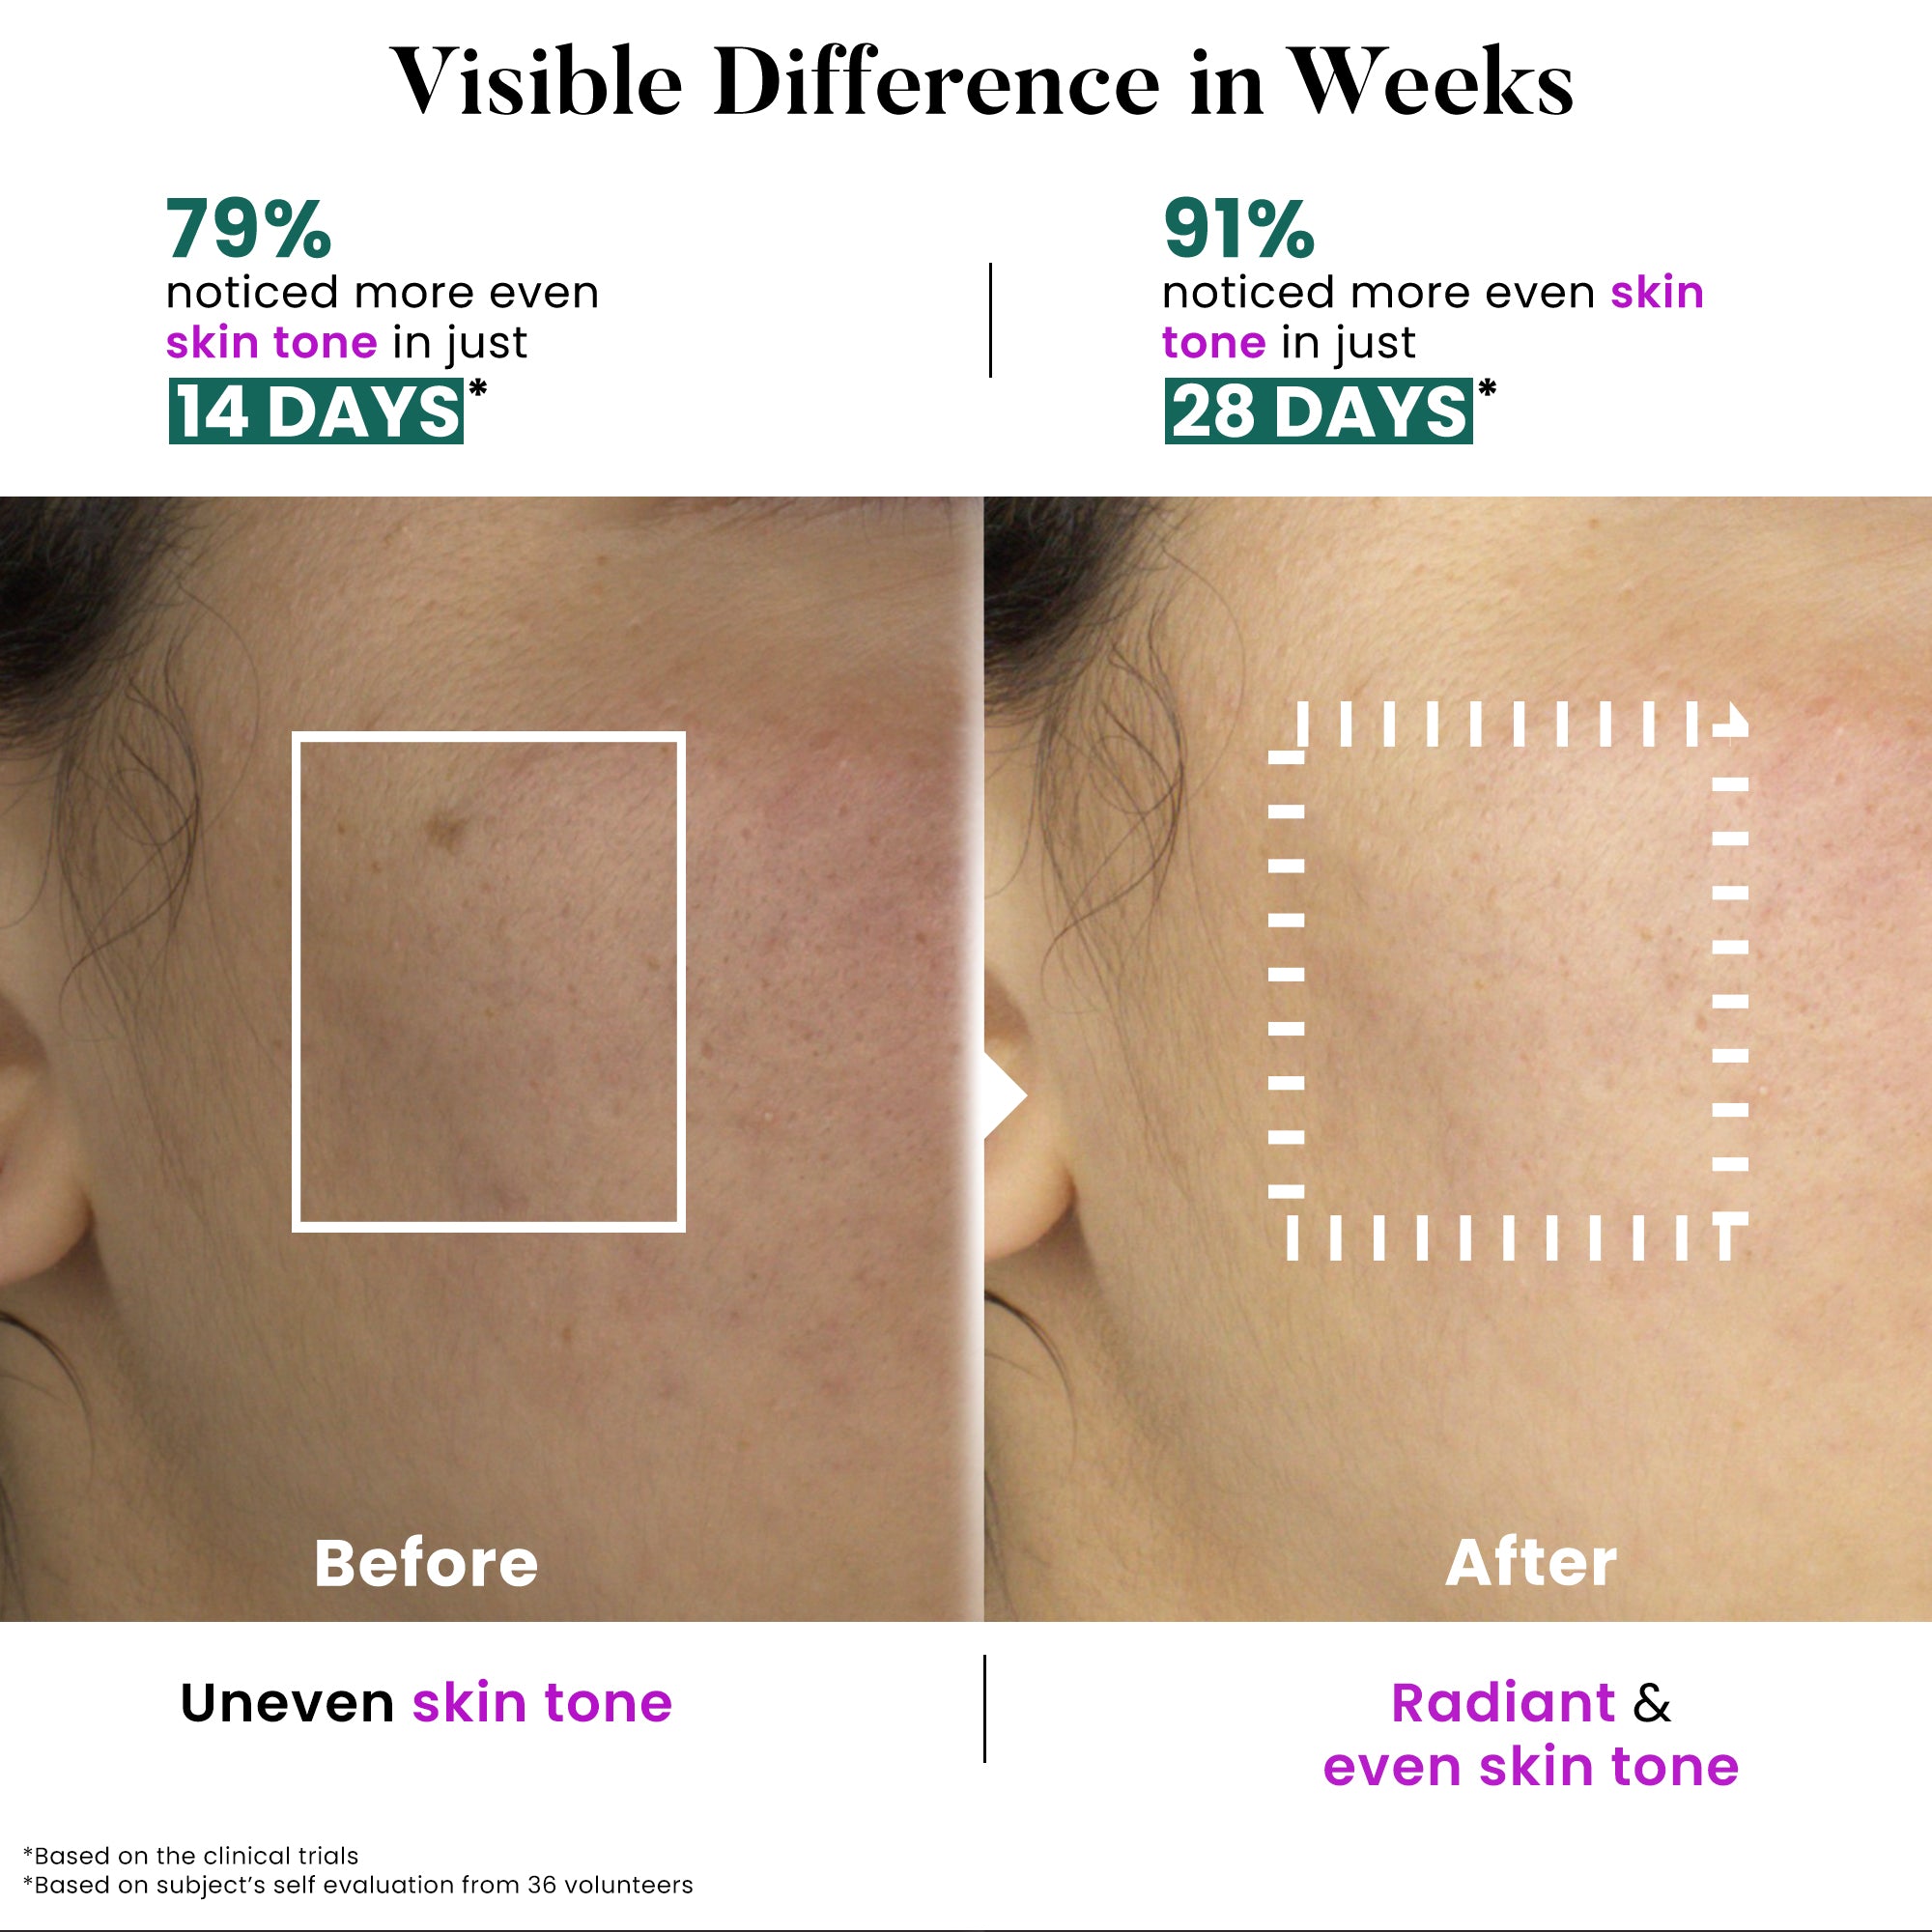

Before

After